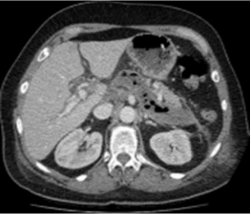

FHC, sexo masculino, 53 anos, na terceira semana de tratamento de pancreatite aguda, realizou a TC de abdome a seguir.

Qual complicação pode ser identificada na TC?